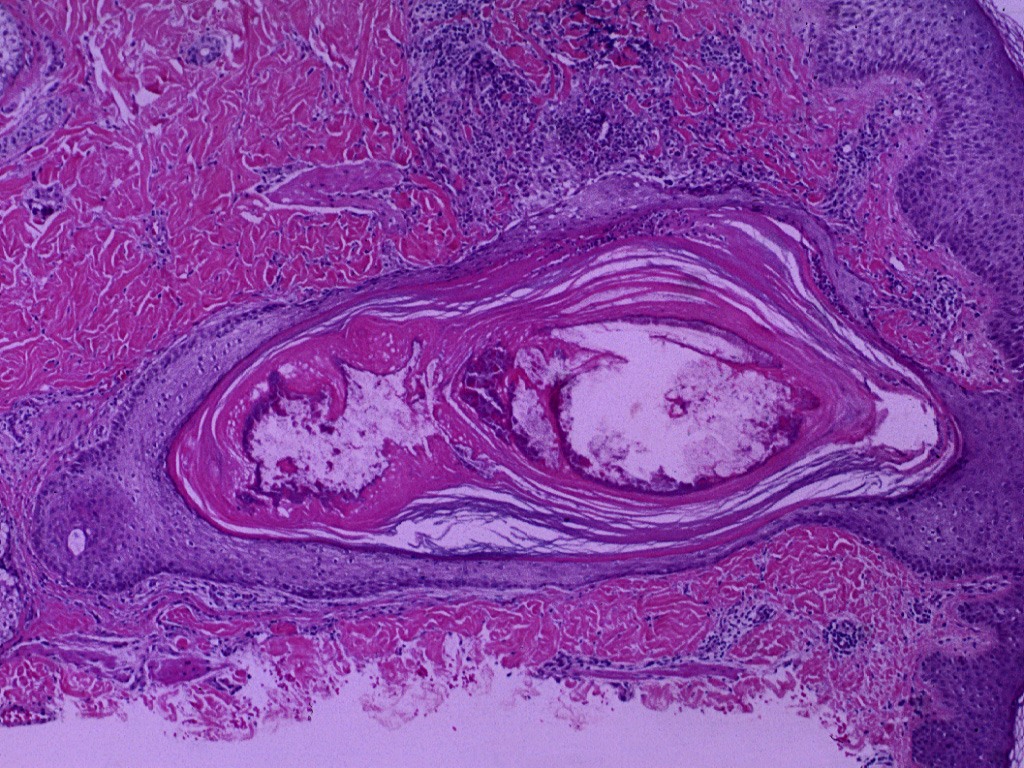

Morton’s Neuroma

Morton’s Neuroma is neuropathic pain in the forefoot and is related to the interdigital nerve (Gougoulias, 2019). It commonly occurs between the second and third metatarsals (Zabaglo, 2020). It is associated with pressure distribution changes in the foot due to either a deformity or calf muscle tightness (Gougoulias, 2019).